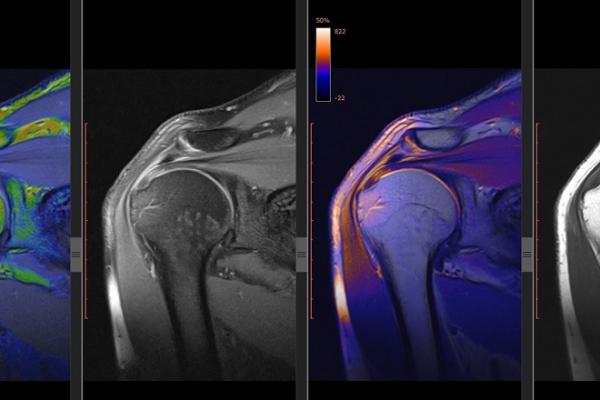

Department of Health follow up letters to GPs - feedback on imaging requests for musculoskeletal concerns

05/11/2020